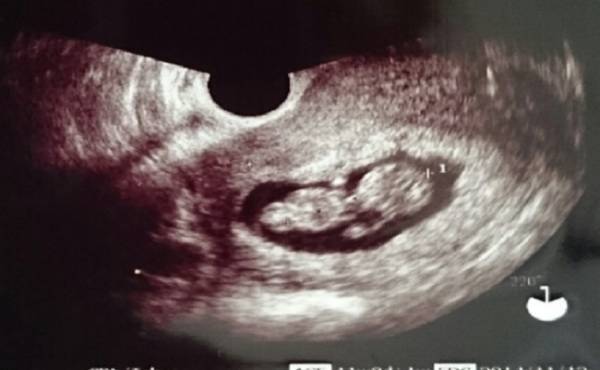

妊娠7カ月、赤ちゃんの心臓病が見つかった

毎回、妊婦健診でおこなう超音波検査。最近では、4D画像も見ることができて、ママにとっても赤ちゃんが見られるうれしい時間でもあります。このエコー、先生が見ているのは胎児の推定体重や性別だけではありません。

白黒の映像の中でも見ることのできる内臓や血管があり、異常がないか先生は見ているのだそうです。

私は妊娠7カ月のころ、赤ちゃんの心臓病が見つかりました。エコーではっきりと、心臓の中の形が見えたことを覚えています。